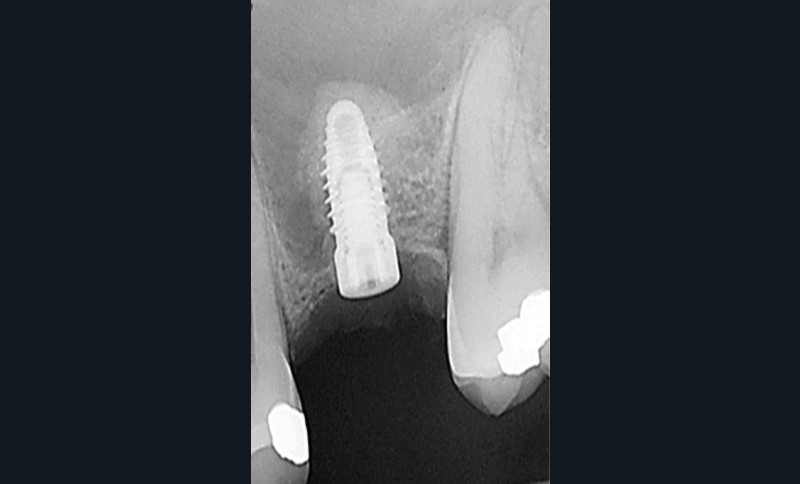

La technique d’élévation par voie crestale décrite par Summers en 1994 [1] est rapportée comme fiable, avec un taux de succès implantaire d’environ 95 % quand la hauteur d’os résiduel est supérieure à 5 mm et que le gain attendu d’élévation de la membrane de Schneider est limité à 4 mm (fig. 1). La complication la plus fréquente est la perforation de cette membrane.

L’étude conduite à Bordeaux vise à valider une nouvelle forme d’ostéotome (fig. 2) dont l’architecture permettrait un protocole plus efficient en termes d’impaction et de fracture du fragment osseux sous-sinusien sans déchirure de la membrane. Trente-trois pièces anatomiques humaines fraîches [2] ont été utilisées pour réaliser des élévations sinusiennes par voie crestale de 4 et 8 mm en utilisant le protocole décrit avec cet instrument. L’intégrité et le comportement de la membrane sinusienne ont été analysés et les résultats montrent l’efficacité du protocole…